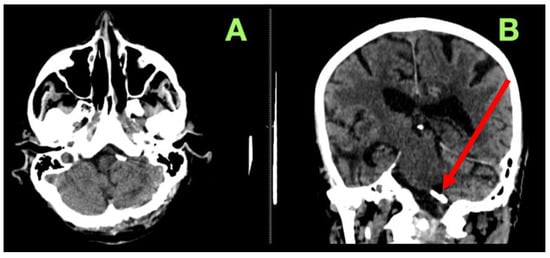

2. Case Presentation